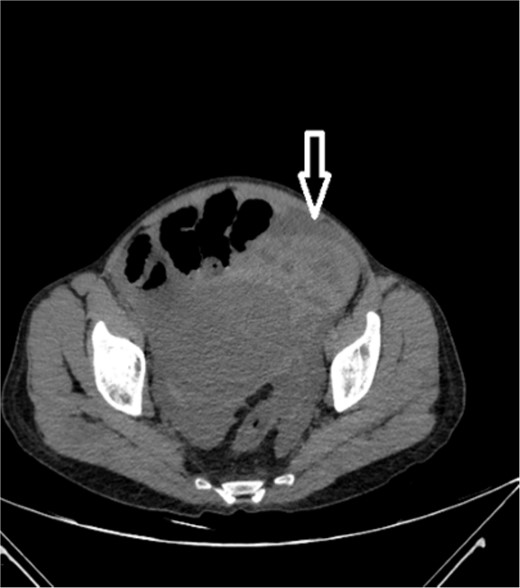

Upon admission to our hospital, the patient’s physical examination revealed hypotension (87/52 mmHg) and tachycardia (150 bpm), along with marked diffuse abdominal tenderness and guarding. Laboratory investigations indicated a hemoglobin level of 7.1 g/dl, a white blood cell count of 14.5 × 103 μl, and a platelet count of 202 × 103 μl. An abdominal CT scan without contrast showed an enlarged ectopic spleen measuring 18 cm in the right abdominal area, a distended stomach, a moderate volume of hemoperitoneum, and significant intra-abdominal fluid accumulation. CT findings are shown in Figs 1–3. Based on these findings, the patient was immediately transferred to the operating room.

Noncontrast axial CT scan of the abdominopelvic area showing a left-sided pelvic hematoma.